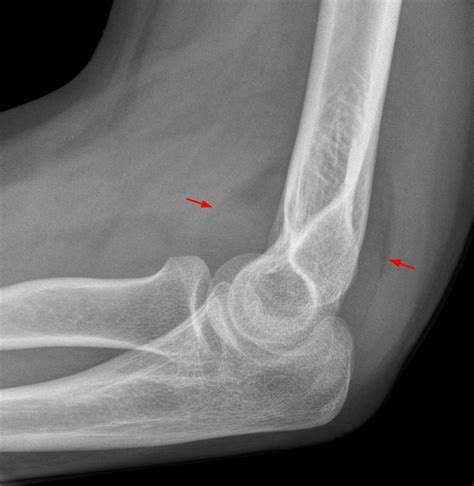

Diagnosing Elbow Hairline Fractures

Diagnosing an elbow hairline fracture typically involves a combination of physical examination and imaging tests. The diagnostic process may include:

• Physical Examination: A healthcare provider will examine the elbow, checking for tenderness, swelling, and range of motion.

• X-Rays: X-rays are the primary imaging tool used to diagnose hairline fractures. They can show the crack in the bone and help determine the extent of the injury.